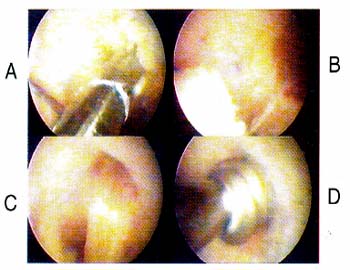

03_01_02_Foto1

Foto 1: Ejemplo de Lesióm vertical longitudinal en zona   Foto 3: Puntos en "U" en el plano vertical dados con rosa.   hilo reabsorvible (Vcril Ng 1)

03_01_02_Foto2

Foto 2: Pasaje de un punto con aguja espinal N= 18, utilizamos nylon 2.0 como pasahilos.

03_01_02_Foto3

Foto 3: Puntos en "U" en el plano vertical dados con hilo reabsorvible (Veril NQ 1)

03_01_02_Foto4

Foto 4: Second-look al mes de suturado el menisco interno (Foto 3) notese la cicatrización de los bordes con reabsorción parcial de los hilos.